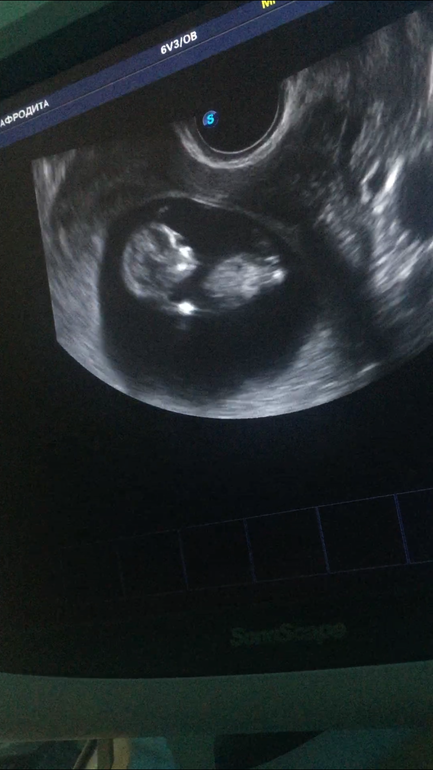

( мне кажется тут пуповина между ног)Вот то что я высмотрела на видео на Первых секундах.

Рядом ножка и бугорок , второй ножки не видно.